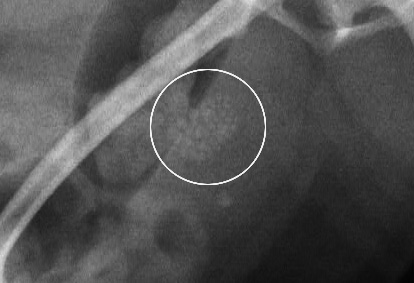

1mm大の結石が多数

酸性尿酸ナトリウム結石

ストルバイト結石